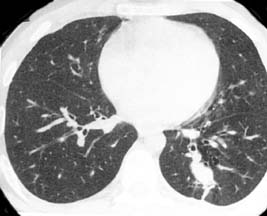

Chest xr-ay

Low dose spiral CT

CT/ CAT scan